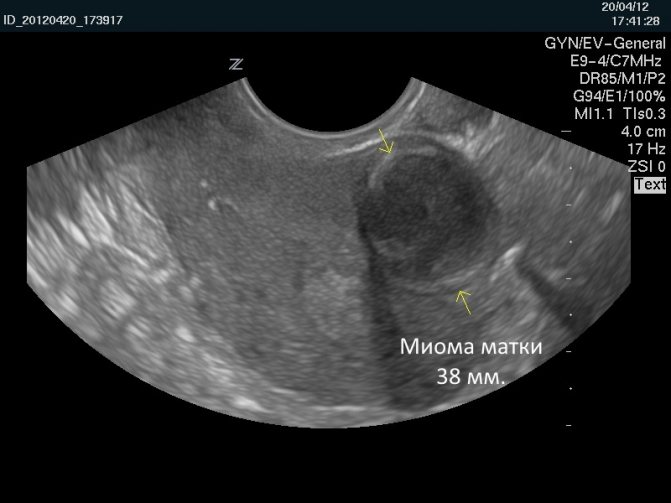

Миома матки 38 мм на УЗИ

Размер миомы определяется с помощью УЗИ. Ее описывают в неделях и в сантиметрах. По мере роста новообразования матка увеличивается так же, как и во время беременности. То есть в случае увеличения матки на 10 неделе беременности женщине ставится диагноз «миома 10 недель». Размеры в неделях и см таковы: